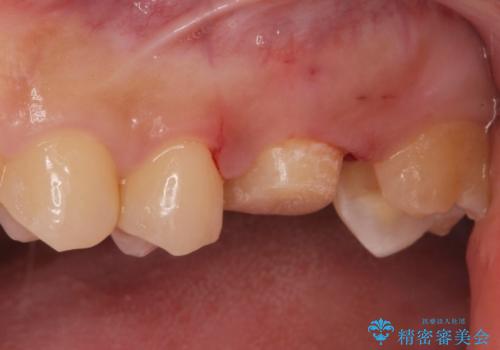

- 金の詰め物の中が黒く透けていて虫歯があるので拡大鏡下で外し、虫歯がない事を確認した後、被せ物で治療しました。

一番奥の歯は古い樹脂の治療の後がありましたのでセラミックの詰め物で治療しました。